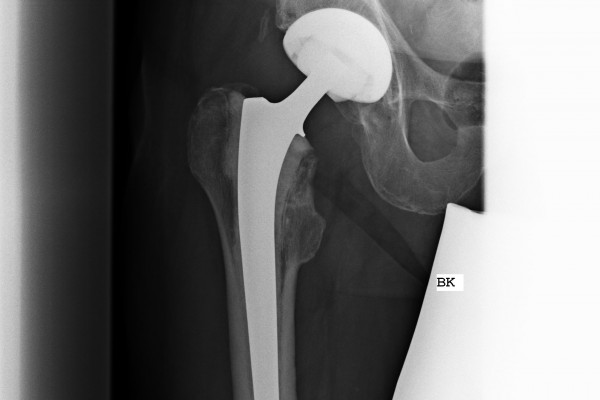

Anatomische Geradschaftprothese

Um bei etwas schlechteren Knochenverhältnissen eine gute Verankerung zu gewährleisten, kombiniert man in diesem Implantat die Vorzüge der klassischen Geradschaftprothese und der anatomischen Kurzschaftprothese. Das heißt, es wird knochensparend implantiert und aufgrund des längeren Schaftes eine gute Verankerung erreicht. Sollte eine Osteoporose vorliegen, kann dieses Prothesendesign auch zementiert eingebracht werden.